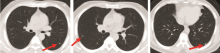

张奕(放射科医师):基于患者的病史和外院CT片, 结合该患者2月份到4月份治疗后复查的情况, 因为该患者肺部的转移瘤在缩小中, 4月份的片中瘤灶基本上消失了, 左上肺有一些囊泡状的空泡影, 考虑为肺气肿(图6)。肺内血行转移小结节有以下三方面的特点:①膨胀性生长, 形态比较饱满, ②多呈类圆形, 边缘比较光滑, ③较少侵犯胸膜。根据以上的特点, 我重新回顾了患者2011年2月的CT片, 逐个小结节分析后认为:左下肺的结节是贴着胸膜塌陷式生长的, 形态不太饱满, 边界也不太光滑。右中肺的几个结节的毛刺非常发达(图7), 意识到以前的诊断有些不对。从图中我们可以清晰地看到, 结节不是特别圆, 边缘不光滑, 形态不饱满, 有塌陷, 有些有毛刺。那么这些小结节是否为转移灶?从影像学上来说, 有以下几点支持转移:①多发小结节, ②肿瘤病史; 以下几点不支持转移:①多处病灶位于胸膜处, 并有牵拉征象, ②多处病灶可见长毛刺, ③多处病灶可见塌陷, 形态欠饱满。至此我们认为, 2月份新发病灶的影像诊断应该是炎性肉芽肿。我们的诊断前后不同, 说明我们对病史的了解和图像的观察不够深入。图8是比较典型的炎性肉芽肿(A、B)和转移瘤病灶(C、D)的CT图像。